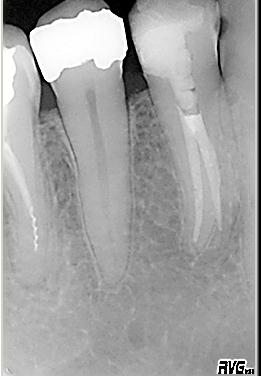

Röntgenologischer Ausgangsbefund

Röntgenologischer Ausgangsbefund im Juli 2002 bei Zahn 44 mit cp. Eine Vitalextirpation ist sehr wahrscheinlich. Als sicheres Zeichen für das Vorhandensein zweier Kanalsysteme ist das scheinbar abrupte Verschwinden des im koronalen Wurzeldrittels deutlich sichtbaren „Pulpastumpfes“ zu werten

Röntgenmessaufnahme

Röntgenmessaufnahme nach vorgängig durchgeführter endometrischer Längenbestimmung

Wurzelfüllung

Wurzelfüllung in lateraler Kondensation mit genormter Guttapercha und AH 26 im Juli 2002